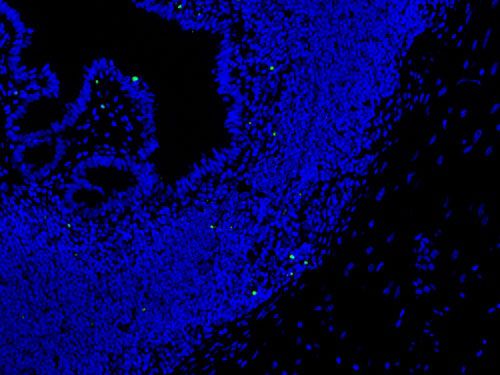

TUNEL(熒光)檢測-小鼠卵巢

TUNEL(熒光)檢測-小鼠腸

晚期凋亡細胞中染色體DNA雙鏈或單鏈斷裂產生粘性3'-OH末端,在脫氧核糖核苷酸末端轉移酶(TdT)的催化下,將帶有熒光素分子的dUTP標記到DNA的3'-末端,然后通過熒光顯微鏡觀察、或進而用帶有HRP的一抗染色后DAB顯色,可以進行凋亡細胞的檢測,該實驗稱為脫氧核糖核苷酸末端轉移酶介導的缺口末端標記法(terminal-deoxynucleotidyl transferase mediated nick end labeling, TUNEL)。

脫蠟至水--蛋白酶K修復--破膜通透--孵育tunel反應液--DAPI染核--抗熒光素淬滅劑封片-- 鏡檢拍照